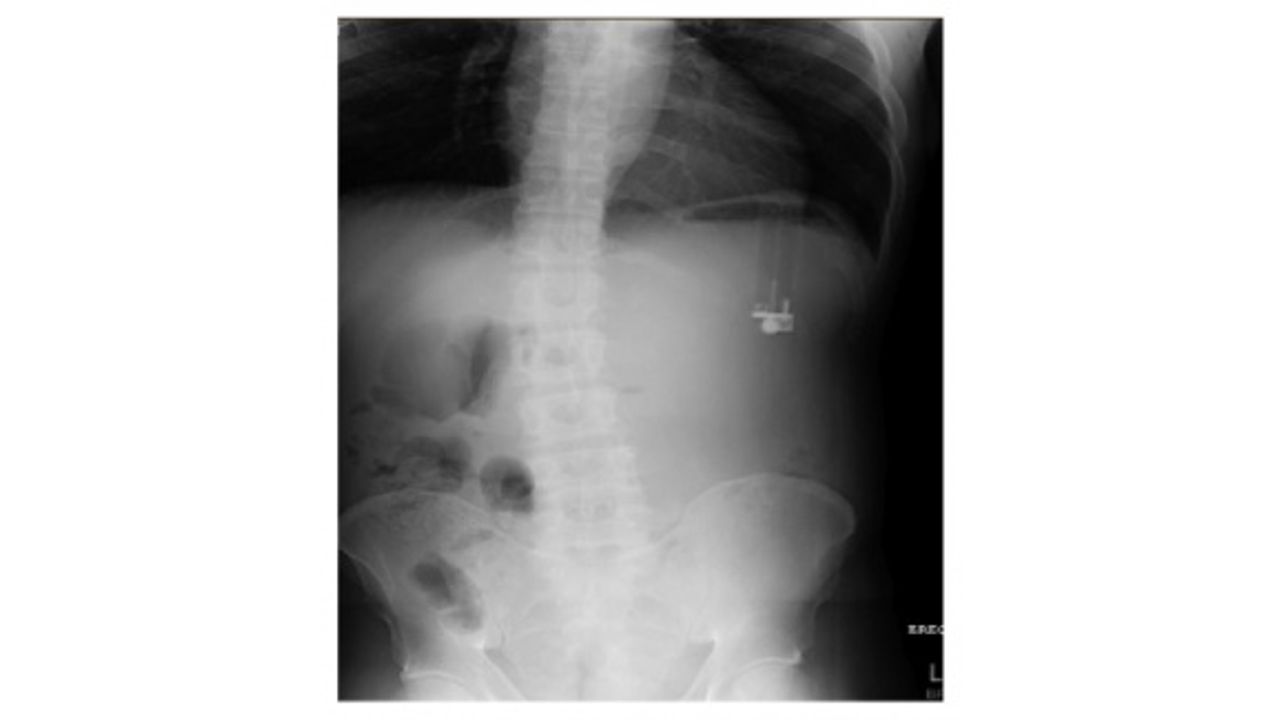

Ağustos 2016'da şiddetli karın ağrısı, mide bulantısı ve istifra şikayetleriyle hastaneye giden 49 yaşındaki Amerikalı adama yapılan kan ve idrar testleri temiz çıkarken, röntgen sonuçlarında çakmak benzeri bir madde görüntülendi. Ağustos 2017'de Case Reports in Emergency Medicine dergisinde yayınlanan makalede, "röntgende görüntülenen çakmağın" adamın midesinde ters bir şekilde durduğu ve mideye zehirli ve kimyasal bir sıvı akıttığı söylendi. Bu sıvı, 49 yaşındaki adamın midesinde en genişi 5 mm olmak üzere, birçok gastrit-ülser yarası oluşmasına sebep oldu.

Makalede, "Çakmaklar hem vücutta tıkanmaya sebep olma hem de vücuda zarar verecek sıvı akıtma nedenleriyle oldukça eşsiz bir problem. Çakmakların akıttığı sıvılarda bulunan zararlı maddeler arasında benzin, bütan, heksamin, gazyağı ve propan bulunuyor" denildi.

49 yaşındaki adamın kendi mide asidiyle birleşen çakmağın akıttığı sıvı, midede gastrit yaralarının oluşmasına sebep oldu. Zararlı sıvı, mide derisini eriterek mide asidini ortaya çıkardı. Konuyla ilgili Florida Üniversitesi Tıp Fakültesi gastroenterologu Dr. Asim Shuja, "Dış maddeler sebebiyle meydana gelen ülser çok yaygın bir durum değil" dedi.

Endoskopi kullanılarak çıkarılan çakmaktan sonra Amerikalı adam ülseri için sekiz hafta boyunca düzenli ilaç kullandı ve iki ay sonraki doktor kontrolünde ülserin iyileştiği belirtildi.